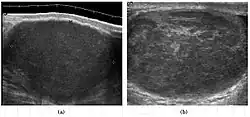

Seminoma is the most common tumor type in cryptorchid testes. The risk of developing a seminoma is increased in patients with cryptorchidism, even after orchiopexy. There is an increased incidence of malignancy developing in the contralateral testis too, hence sonography is sometimes used to screen for an occult tumor in the remaining testis. On US images, seminomas are generally uniformly hypoechoic, larger tumors may be more heterogeneous [Fig. 3]. Seminomas are usually confined by the tunica albuginea and rarely extend to peritesticular structures. Lymphatic spread to retroperitoneal lymph nodes and hematogenous metastases to lung, brain, or both are evident in about 25% of patients at the time of presentation.

Embryonal cell carcinomas, a more aggressive tumor than seminoma usually occurs in men in their 30s. Although it is the second most common testicular tumor after seminoma, pure embryonal cell carcinoma is rare and constitutes only about 3 percent of the nonseminomatous germ cell tumors. Most of the cases occur in combination with other cell types. At ultrasound, embryonal cell carcinomas are predominantly hypoechoic lesions with ill-defined margins and an inhomogeneous echotexture. Echogenic foci due to hemorrhage, calcification, or fibrosis are commonly seen. Twenty percent of embryonal cell carcinomas have cystic components. The tumor may invade into the tunica albuginea resulting in contour distortion of the testis [Fig. 4].